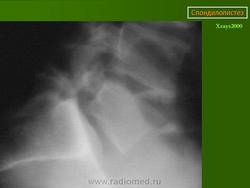

Рис.3a,b,c. Истмический спондилолистез (спондилолиз). a) Рентгенограмма поясничного отдела позвоночника. Стрелкой указана зона дефекта (спондилолиза) дужки L5 позвонка. b) Компьютерная томограмма (КТ) L5 позвонка. Стрелкой указана зона дефекта (спондилолиза) дужки L5 позвонка. с) Магнитно-резонансная томографи (МРТ) поясничного отдела позвоночника. Стрелкой указано смещение L5 позвонка кзади I степени.